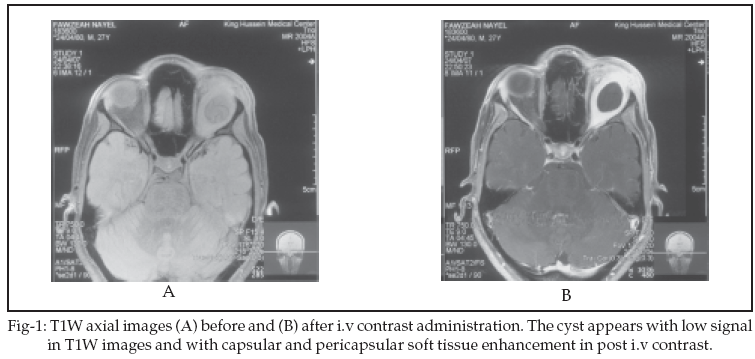

Orbital MRI was done which showed a 2 X 2cm well circumscribed, cystic lesion located solely in the superior rectus muscle. It appeared hypointense in T1W (Figure-1A) and hyperintense in T2W images with internal undulating hypointense membrane (Figure-2B). The internal undulating hypointense membrane is the characteristic appearance of hydatid cyst anywhere in the body. Following I.V contrast injection, the cyst showed thick enhancement of the capsule (Figure-1B, Figure-2A). The patient underwent surgical removal of the cyst by transcranial surgical approach. Post operative examination revealed no proptosis, residual limitation of upgaze occular movement. Postoperative MRI shows no evident of cyst residue.

The main clinical feature of the disease is progressive unilateral proptosis. Other clinical findings include mechanical restriction of occular movements, visual impairment, occular tension or pain, lid edema, papilloedema, and optic atrophy.7,8,12 Upon MRI examination, the cystic lesion appeared low signal on T1W images, high signal on T2W images, capsular and pericapsular soft tissue enhencement, and the capsule was seen as a hypointense rim surrounding the mass on T2W images. Those features were also reported in previous cases.4,5 However, we have also detected an undulating membrane within the hydatid cyst which represent a typical characteristic of the echinococcal cysts in other organs.